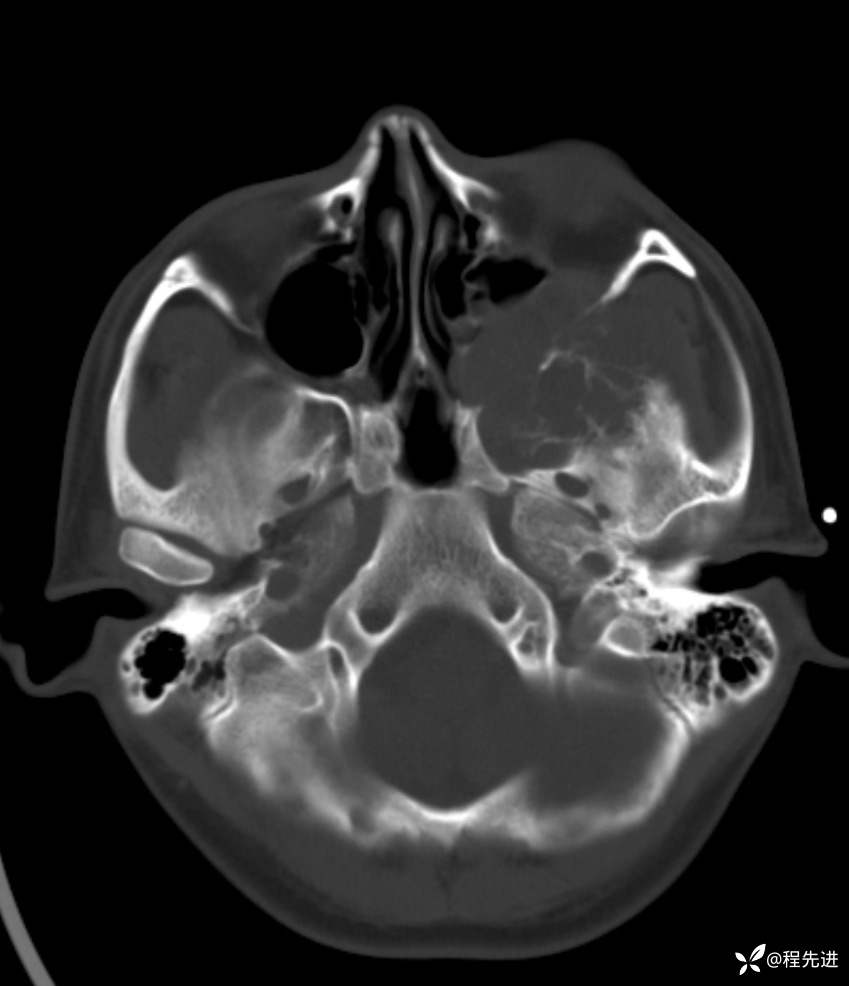

简要病史:左眼视力下降20余天,伴肿胀疼痛不适半月

CT平扫:

骨窗: